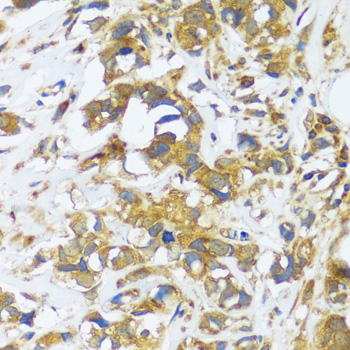

ApplicationWB, IHC; Recommended dilution: WB 1:500 - 1:2000, IHC 1:50 - 1:200